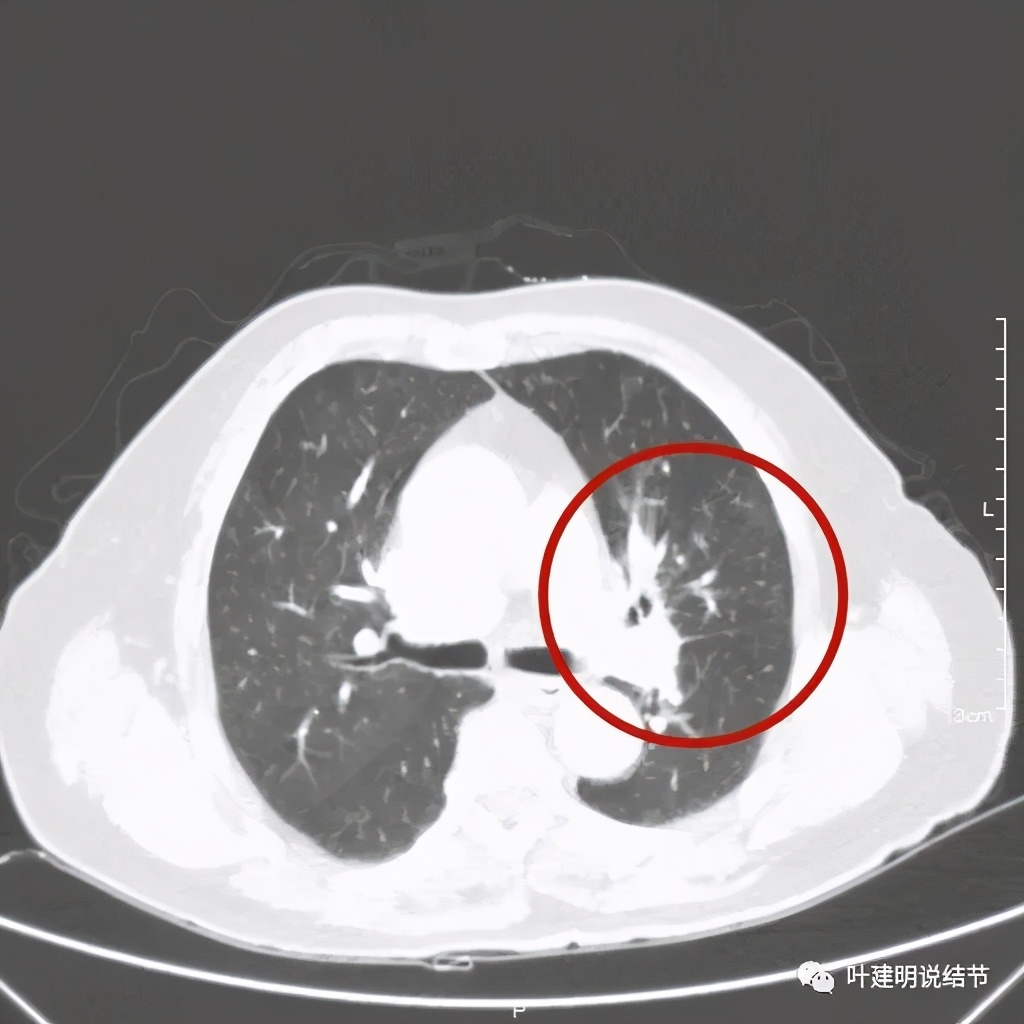

肺窗见原左上叶巨大占位已经明显缩小,甚至几乎不见了!而且上图示左上叶支气管清晰可见,内壁变光滑。纵隔窗增强又是如何的呢?

上图示左上叶开口已经显露出来

上图绿色示左上叶支气管,蓝色示下叶支气管开口处